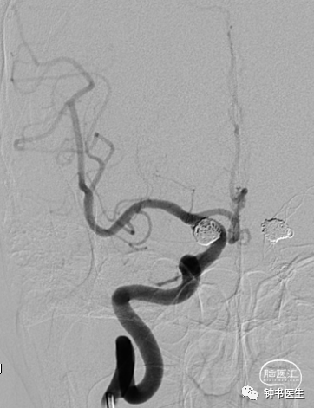

2021-07-05 DSA

Tubridge 4045

TB植入后动脉瘤即刻不显影。